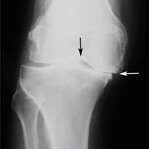

Artrita este inflamația articulațiilor, însoțită de durere puternică și mobilitate limitată. Conform statisticilor, 37% dintre persoanele cu artrită devin invalide dacă nu încep tratamentul la timp. Nu ignora semnele timpurii ale bolii!

Osteoartrita distruge treptat țesutul cartilaginos și duce la deformarea articulațiilor. În timp, chiar și cele mai simple mișcări devin imposibile, iar durerea devine constantă. O terapie corectă ajută la încetinirea progresiei bolii.